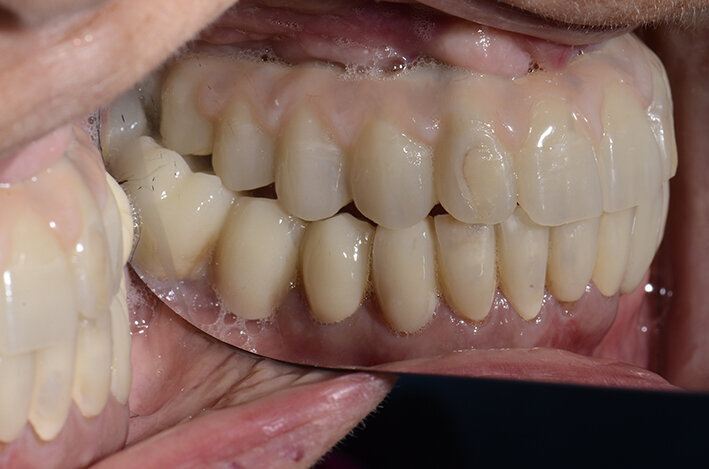

Procediamo quindi all’inserimento di sei impianti BLX Straumann (Straumann Group) (Fig. 43, 44), ed utilizziamo gli impianti posizionati nella tuberosità per stabilizzare la dima chirurgica e il provvisorio sul modello master di lavoro digitale. La funzionalizzazione del provvisorio immediato subito dopo l’intervento viene effettuata con l’utilizzo della tecnica DIL19 (Figg. 45, 46).

Il provvisorio immediato così funzionalizzato creerà un condizionamento ideale dei tessuti (Figg. 47-49) che porterà alla realizzazione del lavoro definitivo con la serenità di aver creato le condizioni per un successo a lungo termine del trattamento. L’immagine dei tessuti a tre mesi dal posizionamento implantare evidenzia i buoni auspici per un mantenimento a lungo termine degli impianti (Fig. 50).